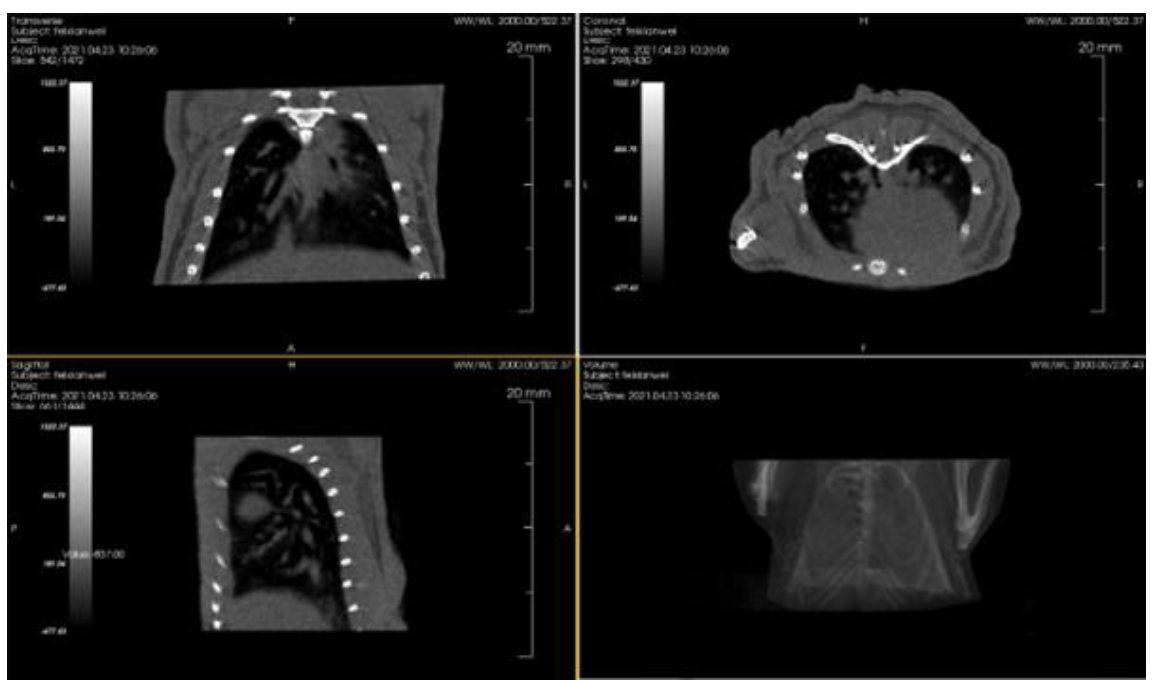

3、肺纤维化药物治疗效果研究